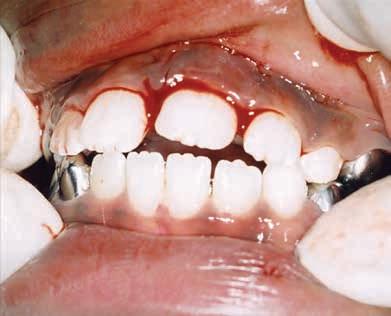

Intraoral assessment revealed that the maxillary left permanent central incisor was intruded 6-7 mm along with buccal displacement. No other extraoral, intraoral or dental injuries were noted. Intraoral radiographs taken confirmed the intrusive luxation injury. The permanent lateral incisors had erupted and the primary canines were not mobile. The initial clinical presentation of the child and associated radiograph are shown in Figure 1. Informed consent was obtained from the patient’s parents to initiate treatment.

Figure 1. Initial clinical presentation and radiograph of the child at approximately 30 minutes of the dental injury.